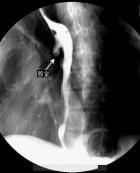

食管憩室(diverticulum of oesophagus)系指與食管相通的囊狀突起。其分類比較繁雜。按發病部位可分為咽食管憩室、食管中段憩室和膈上食管憩室。根據其發病機制不同又分為牽引性、內壓性、牽引內壓性憩室。根據憩室壁的構成可分為真性憩室(含有食管壁全層)和假性憩室(缺少食管壁的肌層)。此外尚可分為先天性憩室和后天性憩室。